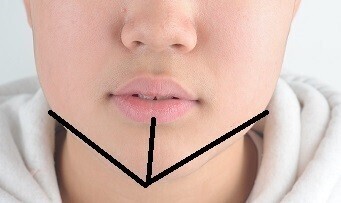

6. 합죽이입매역교정

9. 비수술안면비대칭교정